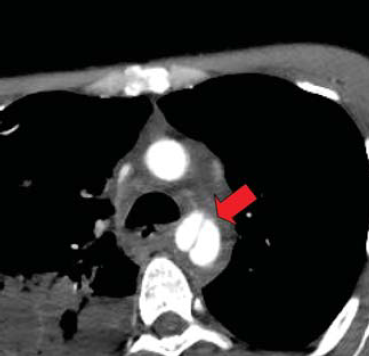

7. sorszámú betegünk CTA vizsgálata multiplex gerinc, borda és jobb oldali acetabulum törés mellett kialkult isthmicus aorta intima sérülését mutatja.

7. 32 éves férfi autóbaleset okozta koponyaűri és arcüregi vérzéssel, agyödémával, kétoldali pleuralis és mediastinalis folyadékgyülemmel, PTX és hasi szabad levegővel, máj és lép körüli kevés véres folyadékkal, felső thoracalis és lumbalis csigolya és jobb lapockatöréssel, jo. acetabulum töréssel, femur luxatioval, kiterjedt mellkas és hasfali subcutan emphysemával, intubálva eszméletlen állapotban került felvételre. Neurologiai statusának rendeződése, mellkasi sérüléseinek ellátása és fracturáinak műtéti rögzítése után, 16 nappal a sérülés követően, a. subclavia transpositiot elvégezve, isthmicus stentgraft beültetés történt. A bal lapockatörés után kialakult dorsalis septicus haematomája 2 hónapos kezelés után gyógyult (6.,7.,8. ábra).

7. ábra.

Előző ábrán bemutatott intima sérülés localis expandáló álaneurysma képződéshez vezetet.

8. ábra.

A gerinc és bordatörések stabilizálása után a sérült aorta szakaszt endografttal fedtük le. Az ábrán jól látható a stent graft nitinol váza.